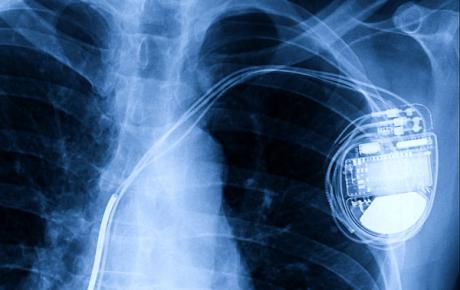

AI-powered wearable devices remotely monitor vital signs, detect abnormalities, and alert healthcare providers, benefiting individuals with chronic conditions by enabling early intervention and reducing hospital readmissions and mortality rates, as seen in the case of implantable heart resynchronisers.